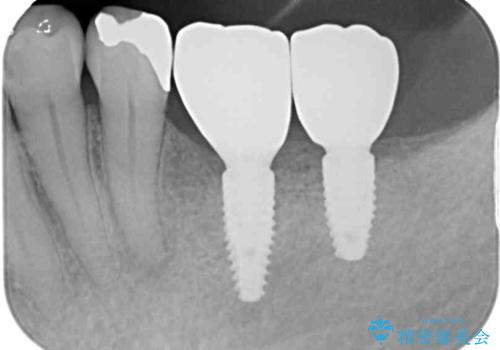

インプラントにはストローマン社のSLActiveを使用し、埋入から補綴までおよそ3か月と、短期間で治療を進めることができました。